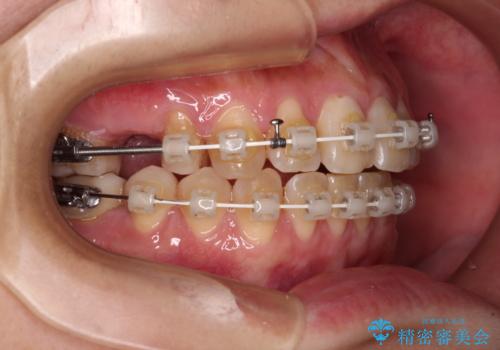

- 奥歯に問題が多くて困っているとのことで来院された患者様です。

開咬により奥歯のみが接触している状態で、前歯部にほとんど接触のない状態で、奥歯に非常に負担のかかる咬み合わせでした。

また、欠損や根管治療の必要な歯など、むし歯による問題も多く散見されました。

まずはむし歯の治療を行い、その後ワイヤー矯正にて咬み合わせを改善し、途中インプラント埋入を行い、矯正治療後に補綴治療を行うこととしました。